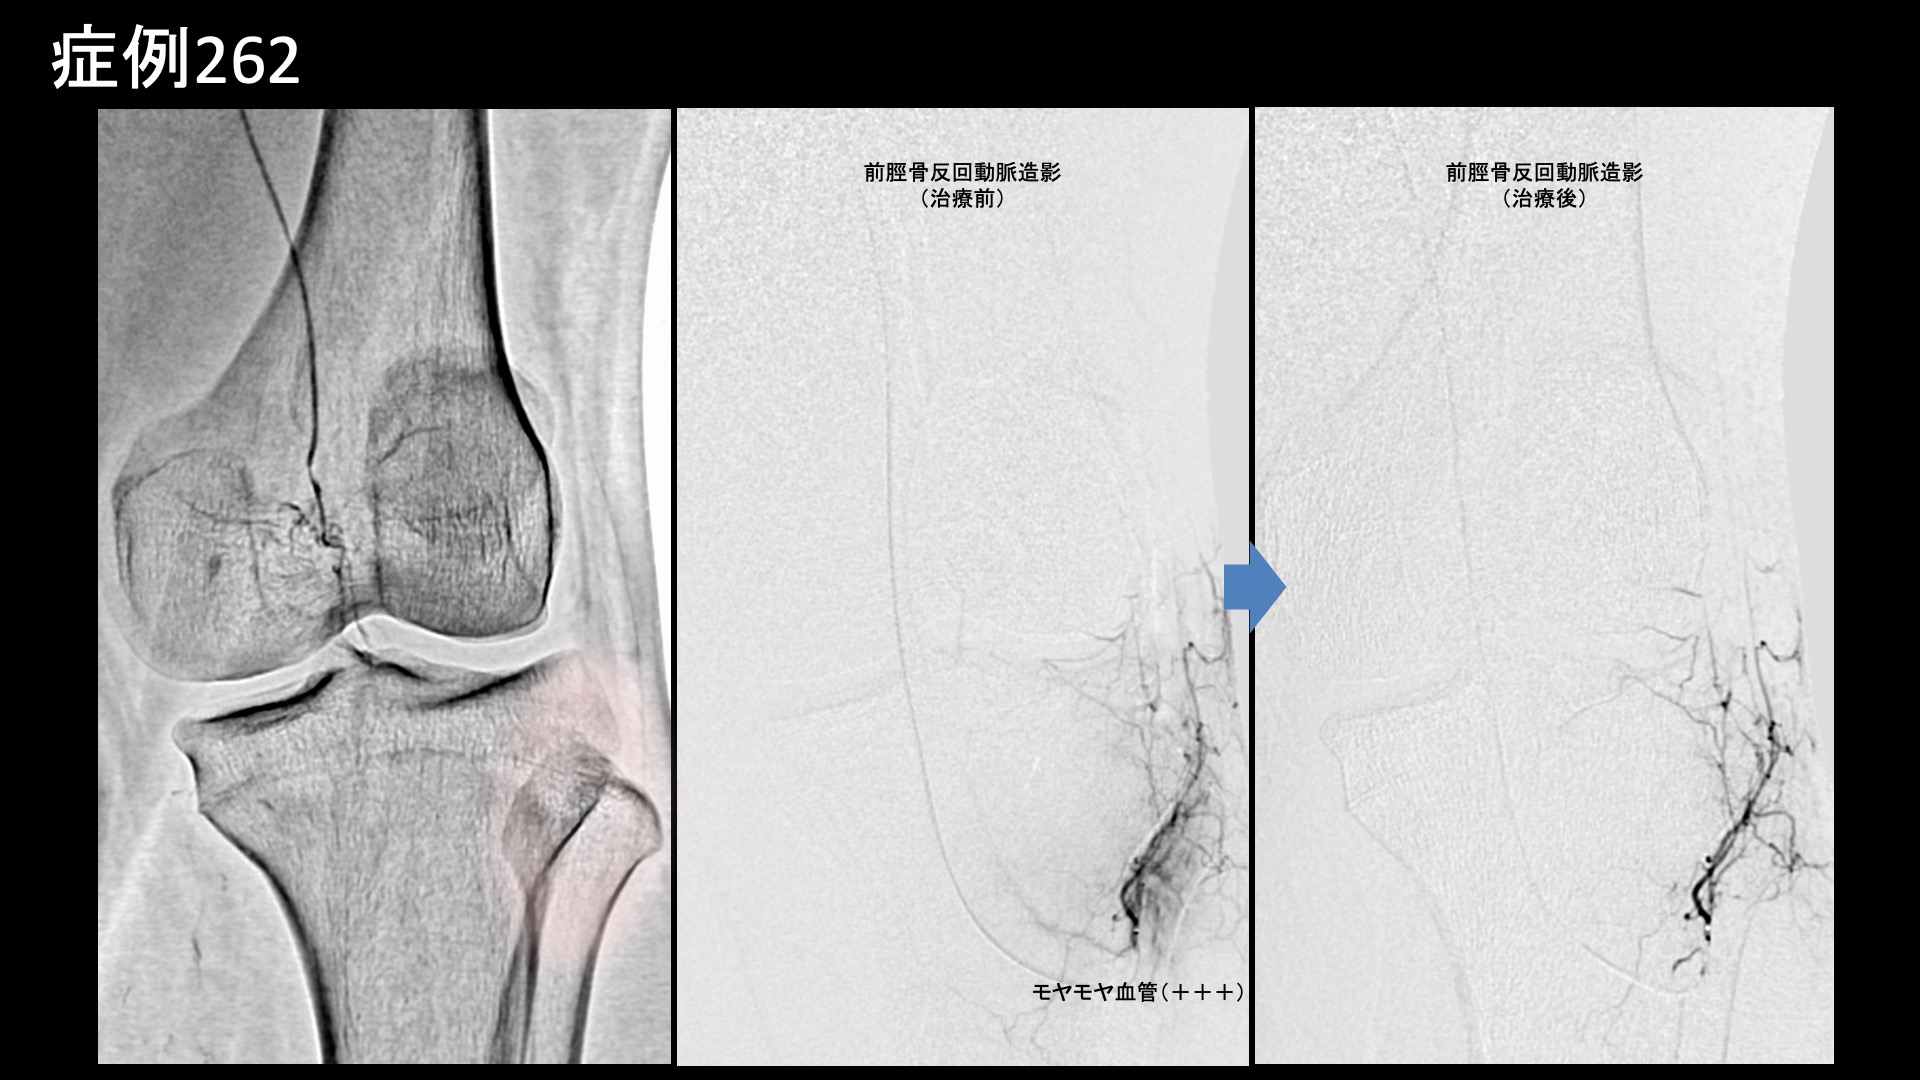

膝:変形性膝関節症など 【20代:男性】パフォーマンス向上のため、スケートボード選手が決断した後縦靭帯損傷後遺症に対するモヤモヤ血管治療(スケートボード、後縦靭帯損傷、外傷後遺症) 2026.02.13 鴨井院長による動画解説 受診までの経過 スケートボード選手です。1年半前から左膝の裏側の痛みがありました。左膝を立てると痛み、ぐっと曲げた時も痛みが増すが、正座までしてしまえば痛くありませんでした。MRI検査の結果、後縦靭帯損傷と診断され、保存的治療の方針となりました。日常生活や軽めの練習では問題ないものの、しっかり曲げられないと競技パフォーマンスを発揮できないことから、治療を決断し当院を受診されました。 診察時の所見 MRI検査にて上記のように確定診断後です。慢性痛に移行しており、モヤモヤ血管の治療適応と判断し、モヤモヤ血管(病的新生血管)に対する運動器カテーテル治療(微細動脈塞栓術)を受けていただきました。 治療の所見 血管造影を行うと、後縦靭帯の血行を担っている中膝動脈に一致して、モヤモヤ血管が濃染像として描出されました。前脛骨反回動脈においても同様にモヤモヤ血管が認められました。特徴的でありご本人に確認したところ、よく打撲する部位とのことでした。繰り返しの打撲により形成されたものと思われました。治療後、これらのモヤモヤ血管は画像上速やかに消失しました。尚、再現痛も一致していました。その他複数箇所の治療を行い終了しました。 *再現痛とは、薬液投与時に普段の痛みが一定程度再現される現象です。責任血管の同定のための参考とします。 治療前画像:損傷を受ける、あるいは繰り返しのストレスにより発生した異常な新生血管 治療後画像:カテーテルを用いて塞栓物質を血管内に投与し新生血管を塞いだ状態 治療費用:治療する部位によって費用が異なりますのでこちらをご参照ください。 主なリスク・副作用等:針を刺した場所が出血により腫れや痛みを生じたり、感染したりすることがあります(穿刺部合併症)。造影剤によるアレルギー(皮膚のかゆみ・赤み・息苦しくなるなどの症状)が出ることがあります。 治療後の経過 治療後2週間、数値で表すのは難しいが、いつも気になっていた部位の痛みが軽減され、問題なく競技ができているとのことでした。治療後1ヶ月半、ぐっと曲げた時に痛むことがなくなりました。転倒した時に気になる痛みもあったのですが、それもあまり痛まなくなりました。十分な練習ができるようになり、パフォーマンスも良好とのことでした。治療後3ヶ月、転倒時の痛みも無くなり、すこぶる調子が良いとご報告いただきました。経過良好であり終診としています。 スポーツ選手の場合、日常生活では困っていないが、競技パフォーマンスに支障をきたす痛みであるということが少なくありませんが、まさにそうした症例であり、パフォーマンスの向上に奏効しました。外傷後の後遺症はモヤモヤ血管治療の良い適応です。中々他に手立てがなくお困りの方も多いと思いますので、ご参考にしていただければと思います。 【60代:女性】発症2ヶ月の帯状疱疹後神経痛(鳩尾~乳房下~背中の痛み)に対するモヤモヤ血管治療(帯状疱疹後神経痛) 前の記事 【50代:女性】顔面に生じた難治の痺れと痛み、顔面骨折に三叉神経第2枝損傷を合併した外傷後疼痛に対するモヤモヤ血管治療(外傷後疼痛、顔面骨折、三叉神経第2枝損傷) 次の記事